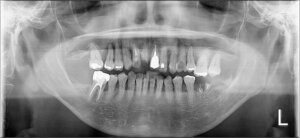

さて、こちらの患者さんの初診時のお口の中の様子をみていきましょう。

前歯が欠けてしまっていて、奥歯は根っこだけになってしまっているところもあります。

さらに、根っこだけになってしまったところを放置したため、挺出してしまっている歯もあります。

そして、レントゲンを見てみると残っている歯も、歯周病で歯を支えている顎の骨がなくなってしまっているのがよく分かります。

この状態では、歯がグラグラしてうまく噛めません。

前歯が欠けてる!

上の歯が挺出している!

大きな虫歯!

歯周病で骨が無い!

これでは噛めない!!